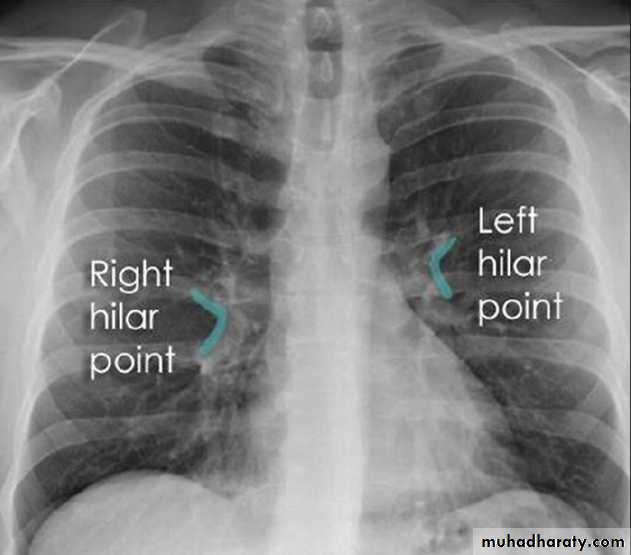

5- hilar shadows: represent the pulm. Arteries and veins.

Air within major bronchi can be recognizes, but walls not usually visible.

Hilar LNs normally too small to seen.

The left hilum usually slightly higher than rt. Side.